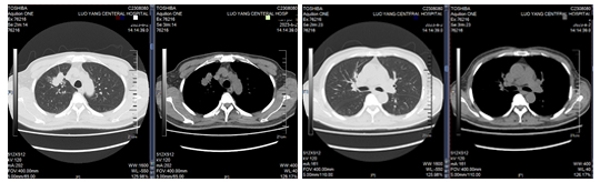

61岁的老陈(化名)近日因血糖控制不佳于洛阳市中心医院内分泌科住院治疗,期间患者要求行肺部健康检查,结果胸部CT提示右肺上叶占位性病变并纵膈淋巴结稍肿大(图1)。患者本人及家属非常紧张,通过内分泌科主管医师请呼吸科会诊,经我院常驻洛阳市中心医院专家董西林教授及洛阳市中心医院呼吸科张娜莉主任共同会诊后,考虑肺结核可能性大,不能除外肿瘤,与患者家属充分沟通病情,并建议转入呼吸科进一步行超声支气管镜检查明确肺部病灶性质,征得患者同意于八月初转至呼吸与危重症医学科三病区进一步诊治。

图1患者胸部CT